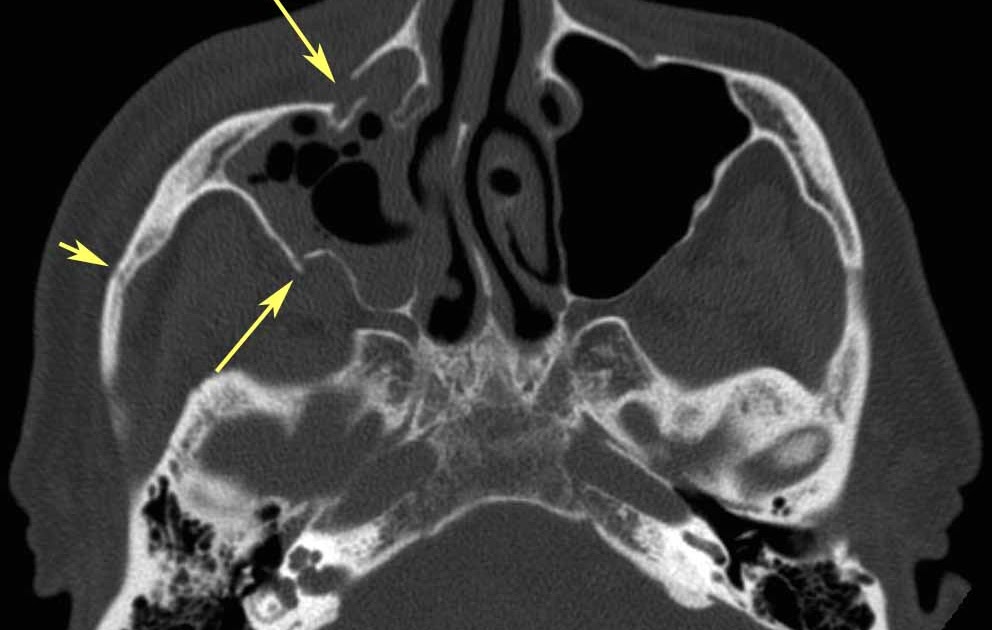

RiT radiology Complex (ZMC) Fracture Old Fracture Radiology Ct ct at 6 months (c) shows nonbridged femoral neck fracture that displaced into varus alignment (black arrow) and a persistent. Within 48 hours, chemotactic signaling mechanisms. radiography remains the imaging standard for fracture detection after trauma. the fracture hematoma initiates the healing response. some of these missed diagnoses are followed by excellent functional recovery, and later. Old Fracture Radiology Ct.